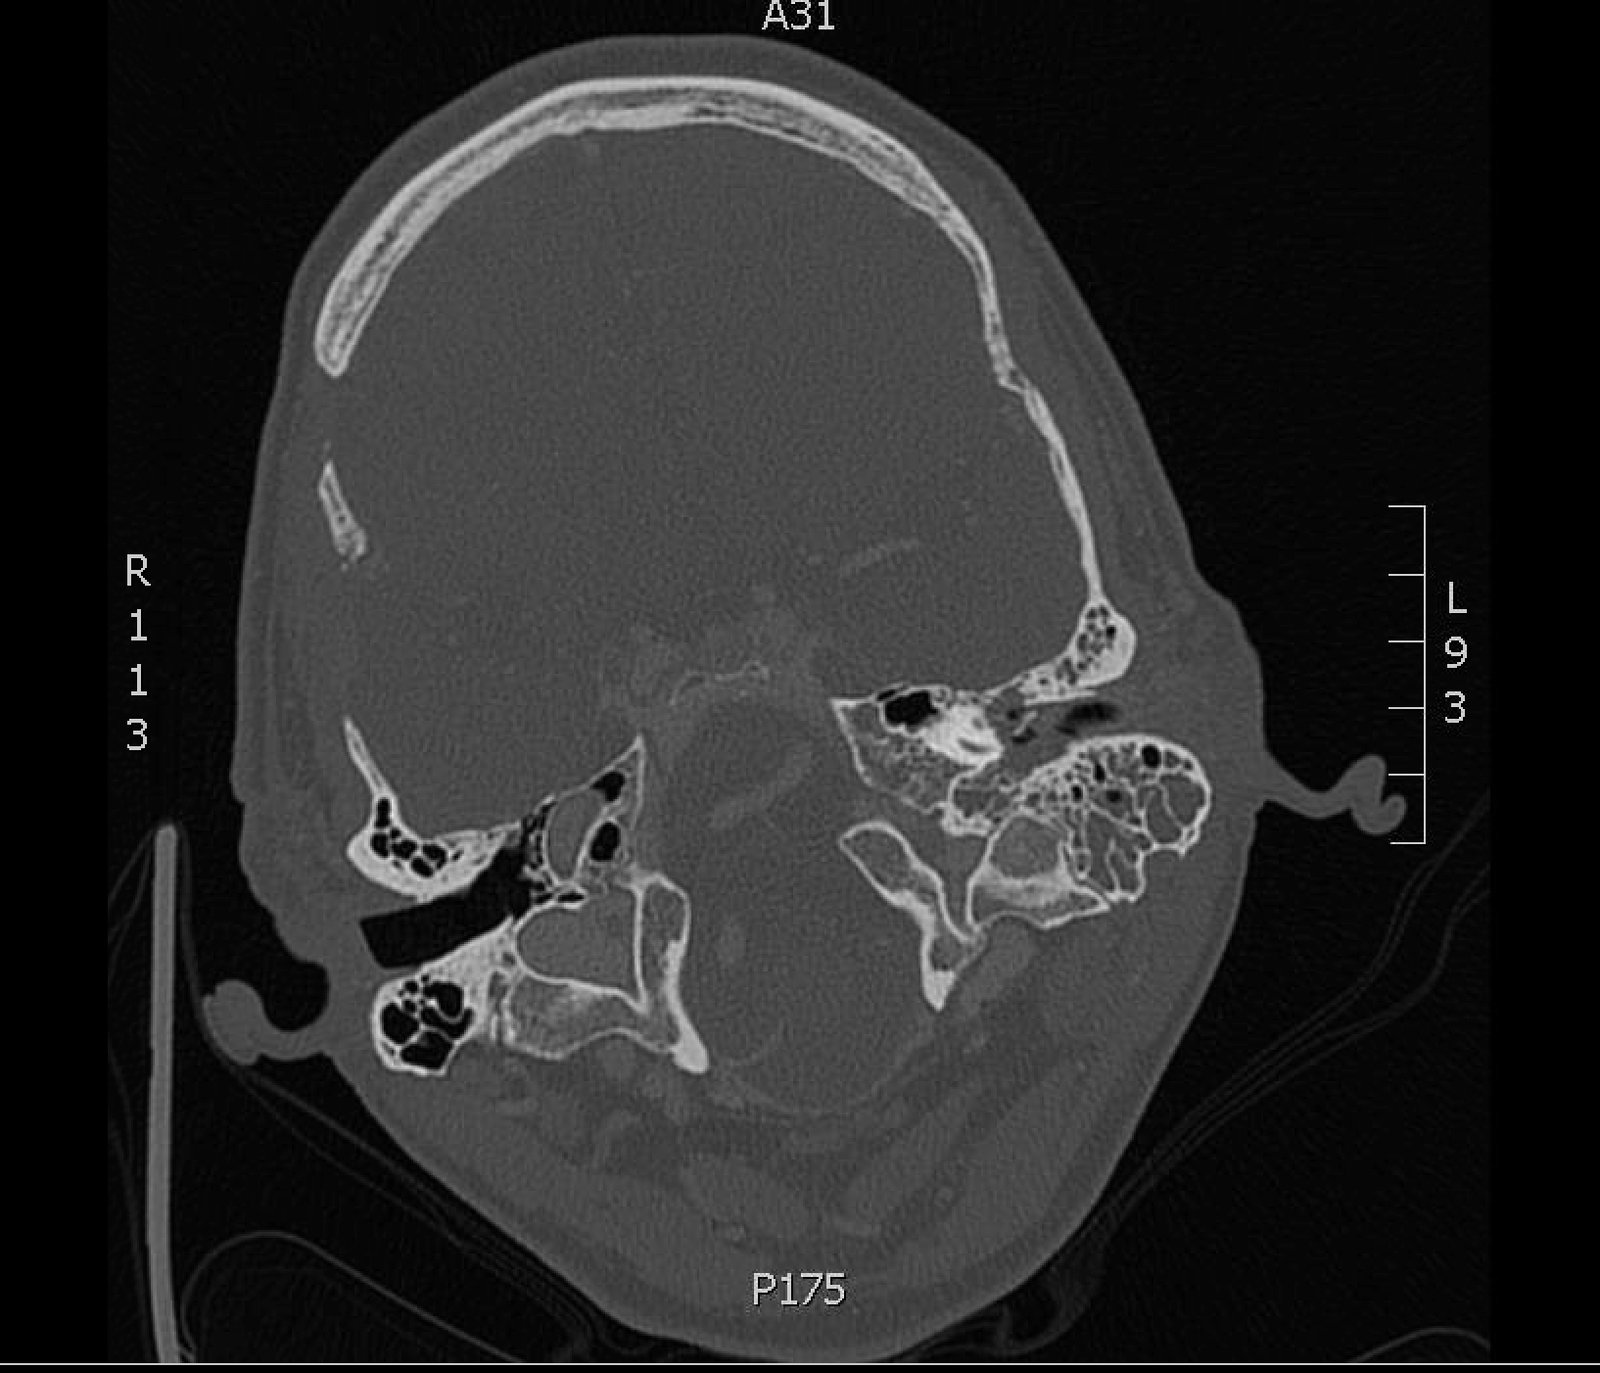

Significant findings:

The patient underwent computed tomography (CT) of the head which revealed opacification of the left middle ear (red arrow) and mastoid air cells (red circles). Additionally, there was thickening of the soft tissues of the external auditory canal (blue arrowhead), likely reflecting concurrent otitis externa.  Based on the imaging, he was admitted for findings consistent with acute otomastoiditis.